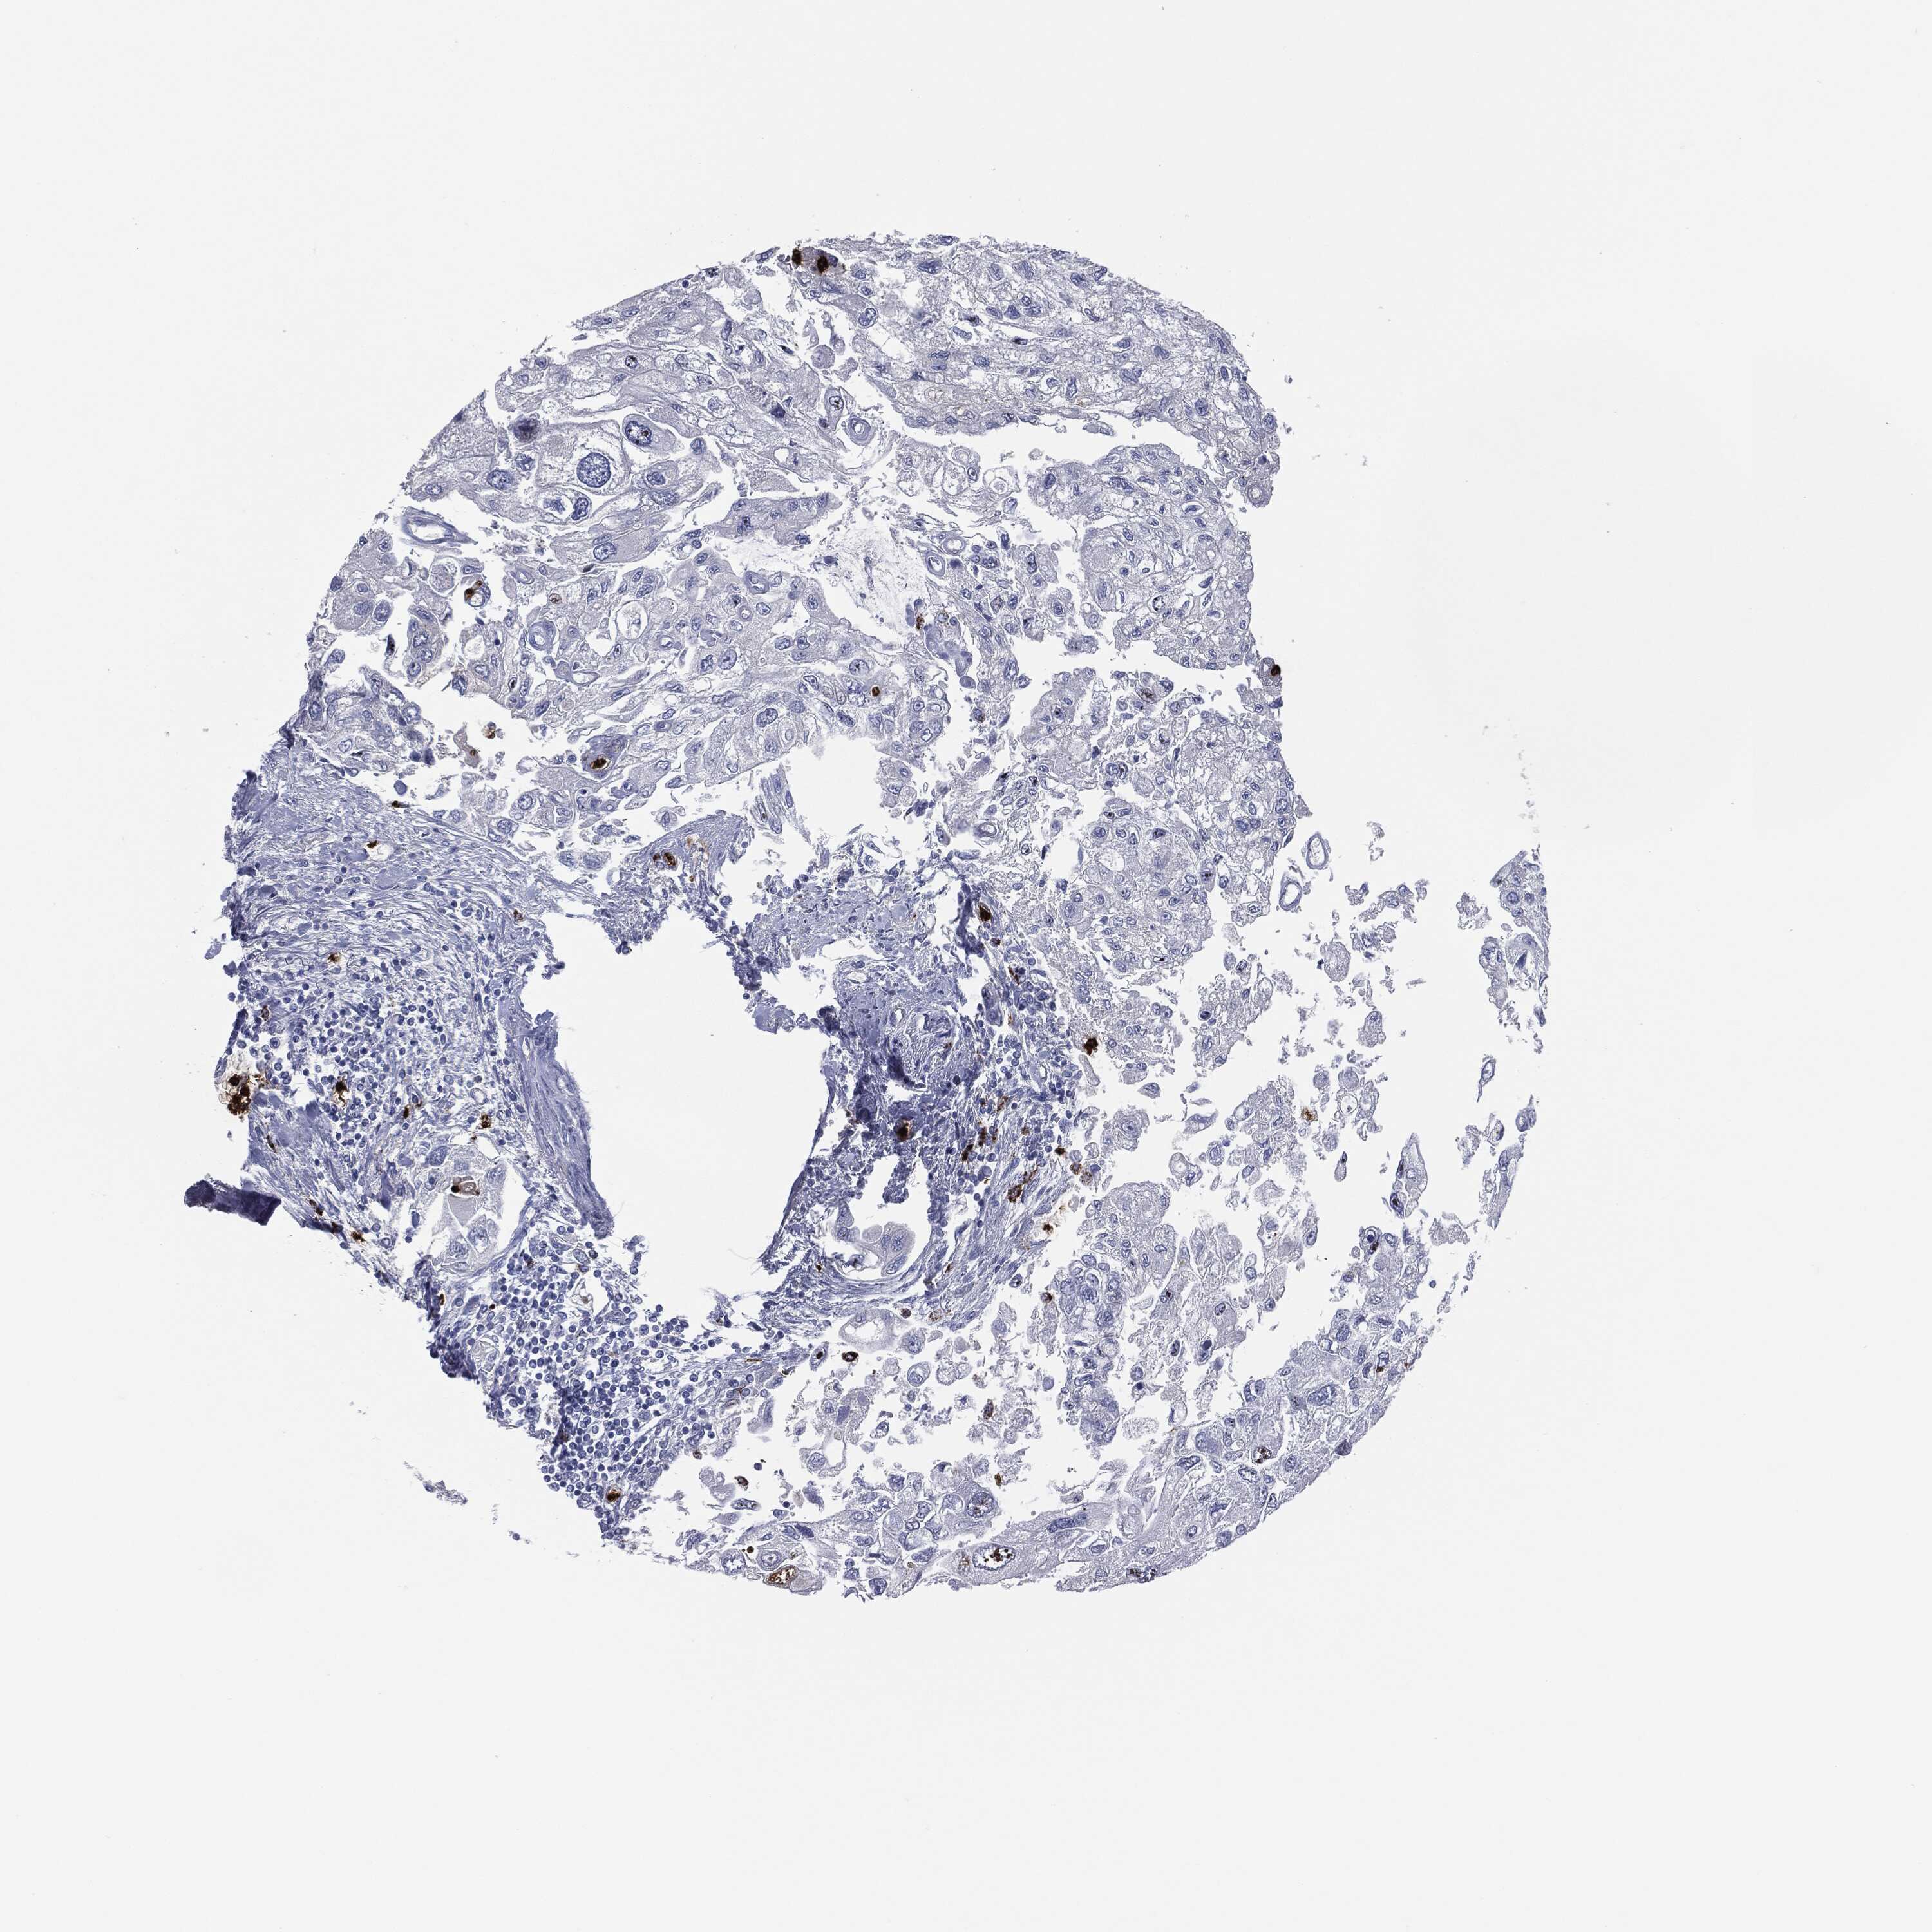

UROTHELIAL CANCER - Protein expressioni

A mouse-over function shows sample information and annotation data. Click on an image to view it in a full screen mode. Samples can be filtered based on level of antibody staining by selecting one or several of the following categories: high, medium, low and not detected. The assay and annotation is described here.

Note that samples used for immunohistochemistry by the Human Protein Atlas do not correspond to samples in the TCGA dataset.

Antibody stainingi

Antibody staining in the annotated cell types in the current human tissue is reported as not detected, low, medium, or high, based on conventional immunohistochemistry profiling in selected tissues. This score is based on the combination of the staining intensity and fraction of stained cells.

Each image is clickable and will lead to virtual microscopy that enables deeper exploration of all samples and also displays staining intensity scores, fraction scores and subcellular localization as well as patient and tissue information for each sample.

Urothelial carcinoma, High grade

Urothelial carcinoma, Low grade

Urothelial carcinoma, NOS